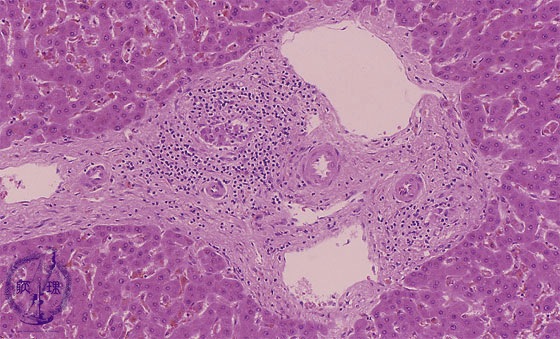

• (11)Transplantation rejection

Microscopic image (HE stain, intermediate power): Mid-sized portal areas show fibrosis and inflammatory infiltrates composed mainly of lymphocytes. Damaged (?) interlobular bile ducts, surrounded by an inflammatory reaction, are gradually destroyed.